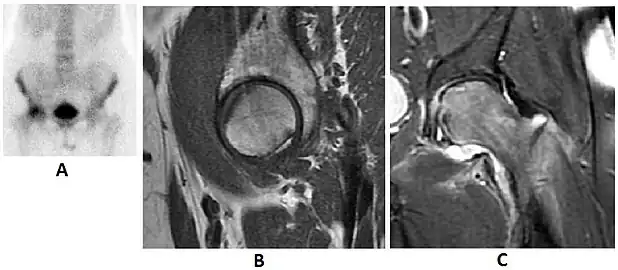

Radiological signs of transient osteoporosis of the hip include localized osteoporosis of the femoral head and neck (Figure 8). Nevertheless, final diagnosis has to be made with MRI to differentiate it from avascular necrosis and from insufficiency or stress fractures of the femoral head or neck. In case of AVN, radiographs can only demonstrate delayed or advanced signs. Staging according to Ficat classification ranges between normal appearance (stage I), slight increased density in the femoral head (stage II), subchondral collapse of the femoral head with or without “crescent” sign (stage III), and advanced collapse with secondary osteoarthritis (stage IV). In the case of stress or insufficiency fractures X-ray sensitivity has been proven to be much lower than MRI, which is currently the gold standard.[1]

Figure 8:

X-ray of a patient with transient osteoporosis of the left hip showing osteoporosis.[1]

Coronal stir imaging in transient osteoporosis, showing diffuse edema.[1]

Scintigraphy (A), sagittal T1 (B), and coronal PD fat sat of a patient with a subchondral fracture of the femoral head with convex shape to the articular surface.[1]

Coronal T1 of a patient with avascular necrosis of the femoral head.[1]

Intra-articular osseous causes of pain include several conditions: avascular necrosis (AVN), transient osteoporosis of the hip (TOH), tumors, and stress or insufficiency fractures. All these entities may present with a pattern of bone marrow edema characterized by decreased signal intensity on T1 weighted images and increased signal intensity on fluid sensitive sequences, such as fat saturated T2-weighted or STIR images. When there is no evidence of a focal lesion associated with the edema pattern, TOH is suspected. When a band of low intensity is seen inside the edematous area, the shape and length of this band become important. It is generally convex to the articular surface in the case of subchondral stress or insufficiency fractures, whereas it is concave, circumscribing all of the necrotic segment, in cases of AVN. When doubts do persist, gadolinium-enhanced MRI tends to show that the proximal portion beyond the band is enhanced in fractures but is not in AVN.[1]

MRI has been shown to have 100% sensitivity and specificity in prospective studies of occult hip fractures. These fractures were diagnosed by bone marrow edema and a low signal fracture line, mainly on T1 or T2 weighted images (Figure 10).[1]